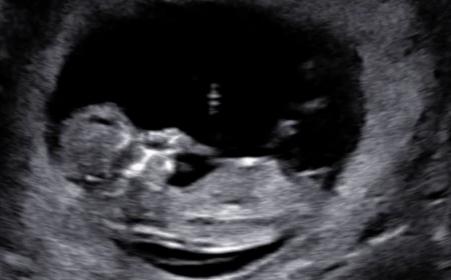

Just finished with NT scan and by lmp im 11w6d (although clinic said 12 weeks) and baby measures ahead at 12w5d. Any more thoughts with these? I have a video too but cant figure out how to blank out my name in it lol.

Attachment 27789Attachment 27790Attachment 27791Attachment 27792Attachment 27793Attachment 27794Attachment 27795

Wanted to update that i got my Mat21 results back and we are having a girl :)

THat is great news! Sorry I missed your recent pics, they were super girly too!!! :)